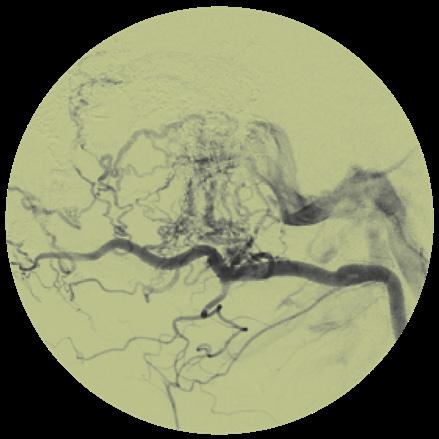

Musculoskeletal (MSK) embolization has steadily gained ground as a minimally invasive option for chronic joint and tendon pain in selected patients. Once primarily associated with interventional oncology (IO) and haemorrhage control, embolization has been applied to conditions such as osteoarthritis (OA), tendinopathies and adhesive capsulitis, with early studies suggesting meaningful pain reduction.

In a session held at the recent Interventionell Radiologisches Olbert Symposium (IROS; 14–17 January, Salzburg, Austria), several speakers described the growing biological rationale underpinning the technique and reviewed available data, emphasising its potential to “break the cycle of pain” in patients with chronic MSK conditions.

In his description of tendinopathy, Alexander Loizides

(Medical University Innsbruck, Innsbruck, Austria) characterises the pain cycle as initiated by the “activation of macrophages” and the subsequent release of inflammatory mediators. This process leads to the development of neoangiogenic factors and the ingrowth of new vessels into the tendons and tendon sheaths. Loizides further notes that this progression involves a “neural component, or a neural cascade,” which significantly contributes to pain generation.

Within this context, the primary objective of embolization is to disrupt the abnormal microvascular supply in the affected tissues. As Loizides explains, the goal is to “interrupt this vicious cycle, breaking the cascade.”

Interrupting the pain cycle: The expanding role of MSK embolization in chronic joint pain

Kraft described treatment for OA and tendinopathy as following a “pyramid model”, beginning with physiotherapy, medication and activity modification, and progressing to injections and other minimally invasive therapies, reserving surgery as the “ultima ratio”.

He continued, defining transarterial embolization in this context as a “minimally invasive, joint-preserving option” for patients who have persistent symptoms despite prior conservative treatment. Kraft added that typical candidates are those experiencing ongoing pain for at least six months with significant impact on quality of life.

Equally, speakers across the IROS 2026 session emphasised that careful patient selection is critical, particularly in younger patients or those who are still candidates for corrective surgery. “Mechanical problems, for example a loose body or a meniscal tear requiring repair, must be treated mechanically,” said Kraft, adding that infections are also a “key contraindication” which is particularly relevant in prosthetic joints.

Upper extremity embolization: Non-linear improvement

While early clinical experience focused largely on knee OA, presenters highlighted that embolization is now

being explored in other regions, including adhesive capsulitis of the shoulder, symptomatic rotator cuff disease, Achilles tendinopathy, plantar fasciitis and selected cases of persistent pain following joint replacement.

Speaking on shoulder applications, Christoph Binkert (Medizinisch Radiologisches Institut, Zürich, Switzerland) observed that “night pain is usually dominant at baseline” and often improves relatively quickly after embolization, whereas improvements in range of motion may occur more gradually. Binkert made clear that, particularly in cases of frozen shoulder, patients must be counselled on expectations regarding pain relief and functional recovery, as he stated that “improvement occurs, but can take time”.

Binkert noted that pain reduction in this area is often “substantial” and can provide long-term relief, but “effects are not always linear”. Additionally, he added that knowledge of the vascular anatomy in upper extremity cases is “crucial” for safe embolization, as there are multiple small branches at risk requiring careful technique to avoid nontarget embolization.

Larger studies needed

Speakers reported that available studies—largely single-arm and observational—suggest that embolization can lead to substantial reductions in pain scores and improvements in quality-oflife measures. Binkert conveyed that approximately 70% of patients show meaningful clinical response in several series and meta-analyses involving the upper extremities.

As Kraft noted during his presentation, the main issue is lack of control groups in these investigations, stating that “without a control arm, interpretation is

difficult, particularly when endpoints are patient-reported outcomes such as pain or function scores”.

Throughout the IROS session, speakers called for larger, multicentre, randomised studies to strengthen the available evidence base, to more clearly define the magnitude and durability of treatment effect in chronic MSK conditions.

Federico Collettini (Charité Universitätsmedizin Berlin, Berlin, Germany), who presented on the current evidence for knee joint embolization, stated that a significant area in need of larger datasets is persistent pain after joint replacement.

We have developed an algorithm: first exclude all other causes: infection, loosening, malalignment, mechanical problems. If everything is excluded and pain persists, embolization of hypervascularised synovium can be considered,” Collettini said.

To date, there are prospective, singlecentre studies showing “significant symptom improvement” with this treatment, but more data are needed to confirm this, he said.

A “shift” toward resorbable particles

Later in the session, Loizides outlined the clinical shift toward using resorbable particles for MSK embolization rather than permanent embolic agents. He highlighted that studies—most notably those by Yuji Okuno et al—have demonstrated favourable outcomes, showing significant pain reduction in the treatment of tendinopathy.

“For tendinopathies, we use imipenem almost exclusively,” Loizides explained, noting its ability to form irregular microparticles that effectively provide occlusion of pathological vessels. A defining characteristic of imipenem is its rapid resorption, with near-complete

dissolution typically within two hours. Loizides further emphasised that meticulous selective catheterisation is paramount, particularly in anatomical regions like the Achilles tendon, which often features a dual arterial supply.

MRI: Necessary or not?

Each of the speakers highlighted the importance of imaging and its central role in identifying target areas, yet, in Kraft’s view, imaging findings are not always a clear indicator of the severity of the patient’s condition. He explained that imaging can show severe radiologic OA, for example, with little pain reported by the patient, whereas mild imaging findings can be accompanied by severe pain.

Binkert underlined that contrastenhanced magnetic resonance imaging (MRI) and MR angiography can help to identify hypervascularised synovial or capsular tissue, and when hyperaemia is present, he added that embolization can be “helpful”. Collettini noted that although contrast-enhanced MRI can help differentiate OA phenotypes and potentially refine patient selection, routine implementation in clinical practice remains challenging in many settings due to cost and limited access.

More to come

Speakers highlighted MSK embolization as a promising but developing technique, emphasising the heterogeneous duration of treatment effect and pain reduction from patient to patient. While early clinical results suggest encouraging pain relief in selected patients, speakers stressed the need for rigorous trials to confirm its efficacy; Collettini stated that therapy decisions in this population are “highly individual”, requiring cautious consideration of symptoms and patient quality of life reports.`